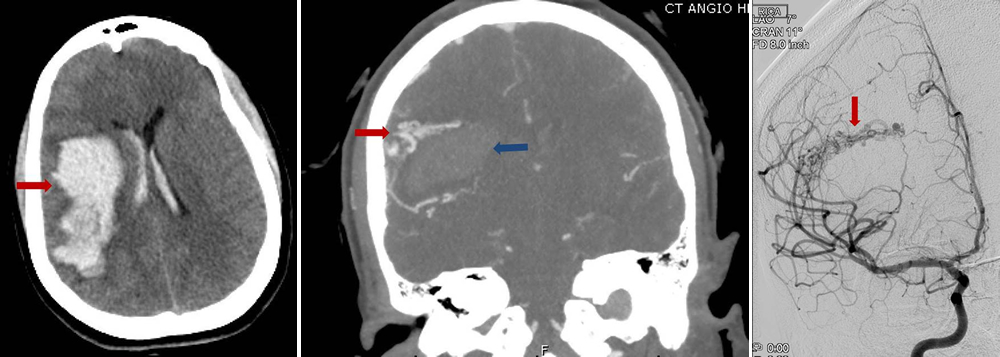

Figure 2: a) Brain CT scan showing bleeding (arrow) in the brain. b) CT angiogram showing bleeding in the brain (blue arrow) and nearby AVM vessels (red arrow) that caused the bleed c) Brain angiogram showing the abnormal vessel tangle (arrow).